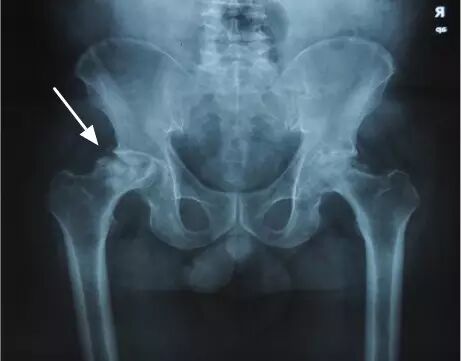

IV期X线片显示股骨头变扁

V期X线片显示关节狭窄或髋臼病变

VI期严重退行性改变

IV期、V期和VI期的患者,由于股骨头坏死已经导致股骨头塌陷变形,所以只能行全髋关节置换术。并且尽量在VI期以前完成手术,因为一旦髋臼出现严重磨损、骨缺损,会显著降低人工关节假体的稳定性和使用寿命。人工关节置换手术以后第二天就可以下地行走,可以下蹲和跑步,不再需要服用药物,生活同常人无异。